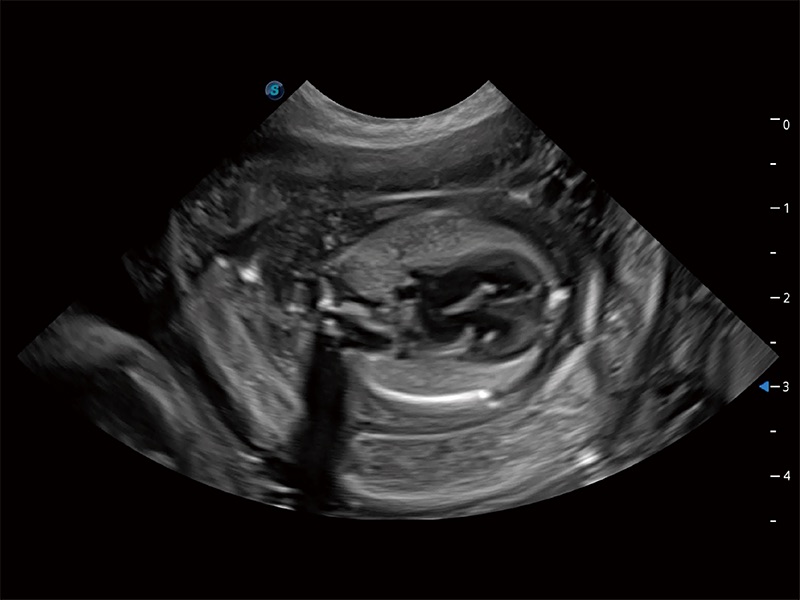

ProPet 80 配备了丰富的心脏探头群、先进的成像技术和专业的心脏测量工具,可帮助动物医生为不同体型和生理结构的动物提供心脏和心肌功能的全面评估。

ProPet 80 专为动物医生设计,对不同的动物体型和生理结构作出了针对性的优化。通过动物影像专用软件,可满足个性化的应用需求,帮助动物医生获得更精确的诊断数据。

ProPet 80 全新的动物超声智能软件和丰富的探头群,为动物医生提供了高清晰度和精细分辨率的图像,无论在宠物、马科、畜牧还是实验室动物等应用中都可以轻松应对,为您的日常工作带来满意的体验。